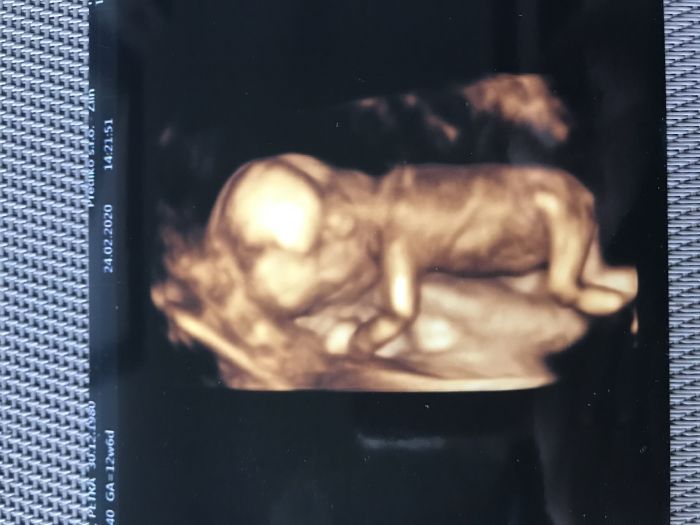

Autor: Petra 24.2.2020 v 17:18

Tak už za sebou máme taky screening v I. trimestru. A všechno OK. Nemůžu tomu ani uvěřit, ze mi všechno v mých letech vyšlo tak krásně. Už jsem byla smířená buď s odběrem plodove vody nebo krve na to neinvazivní testování a prý to není vůbec potřeba. Akorat je mi porad špatně. Když nejim, dostanu hlad až je mi z toho špatně, když se najim, tak je mi špatně. V sobotu jedeme celkem daleko autem, vůbec nevím, jak to dam.